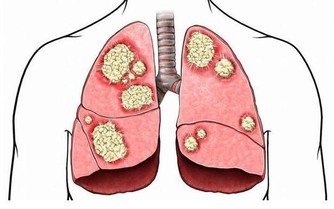

大便中的毒素在體內積累時間過長,有害物質被腸道吸收,就會出現精神委靡不振、頭暈乏力、食慾減退等症狀,嚴重者甚至會引發腸道癌症。

3.容易造成便秘總有些場合,比如長途乘車上、上課考試途中,不能出去方便。「排便習慣不好,大便不規律,憋便都容易造成便秘,這和結腸癌等腫瘤的發生有相關性,但不是決定因素。所以大家也無需神經兮兮動不動就跑廁所,幾天排一次便不代表就吸收了大便中的毒素中毒了。」北京婦產醫院泌尿外科主任馬樂說。